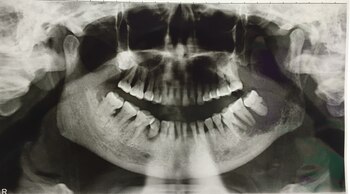

El cáncer oral es una enfermedad que afecta los tejidos de la boca y la garganta, y puede presentarse en los labios, la lengua, las encías, el paladar, las amígdalas o la parte interna de las mejillas. Es importante destacar que el consumo de tabaco y alcohol son factores de riesgo significativos para el desarrollo de cáncer oral. Además, la infección por el virus del papiloma humano (VPH) también puede aumentar el riesgo de padecer esta enfermedad.

Los síntomas del cáncer oral pueden incluir llagas que no cicatrizan, manchas blancas o rojas en la boca, dolor persistente en la boca o garganta, dificultad para tragar o masticar, cambios en la voz y bultos en el cuello. Es fundamental realizar chequeos regulares con un dentista u especialista en salud bucal para detectar cualquier anomalía a tiempo.

La incidencia del cáncer oral en España es significativa, con cifras que varían entre 5,7-12,9 casos por 100.000 hombres/año y 0,6-2,1 casos por 100.000 mujeres/año. Anualmente, se diagnostican más de 8.000 nuevos casos de cáncer oral y de orofaringe en España, siendo esta enfermedad una de las diez más diagnosticadas en el país. Se estima que el cáncer de orofaringe representa el 18% de todos los casos de cáncer de cabeza y cuello, con hasta un 30% atribuible al virus del papiloma humano (VPH).